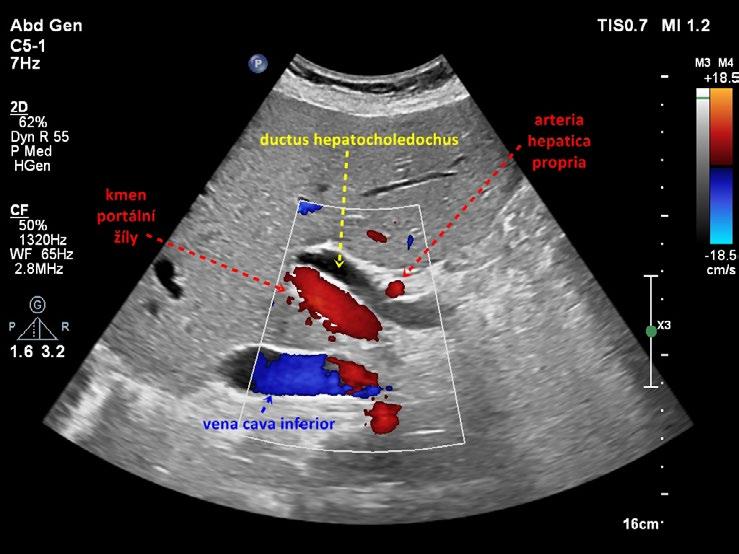

Obr. 1.24 Intrapankreatická část ductus hepatocholedochus

Obr. 1.26 Intrapankreatická část ductus hepatocholedochus podélně